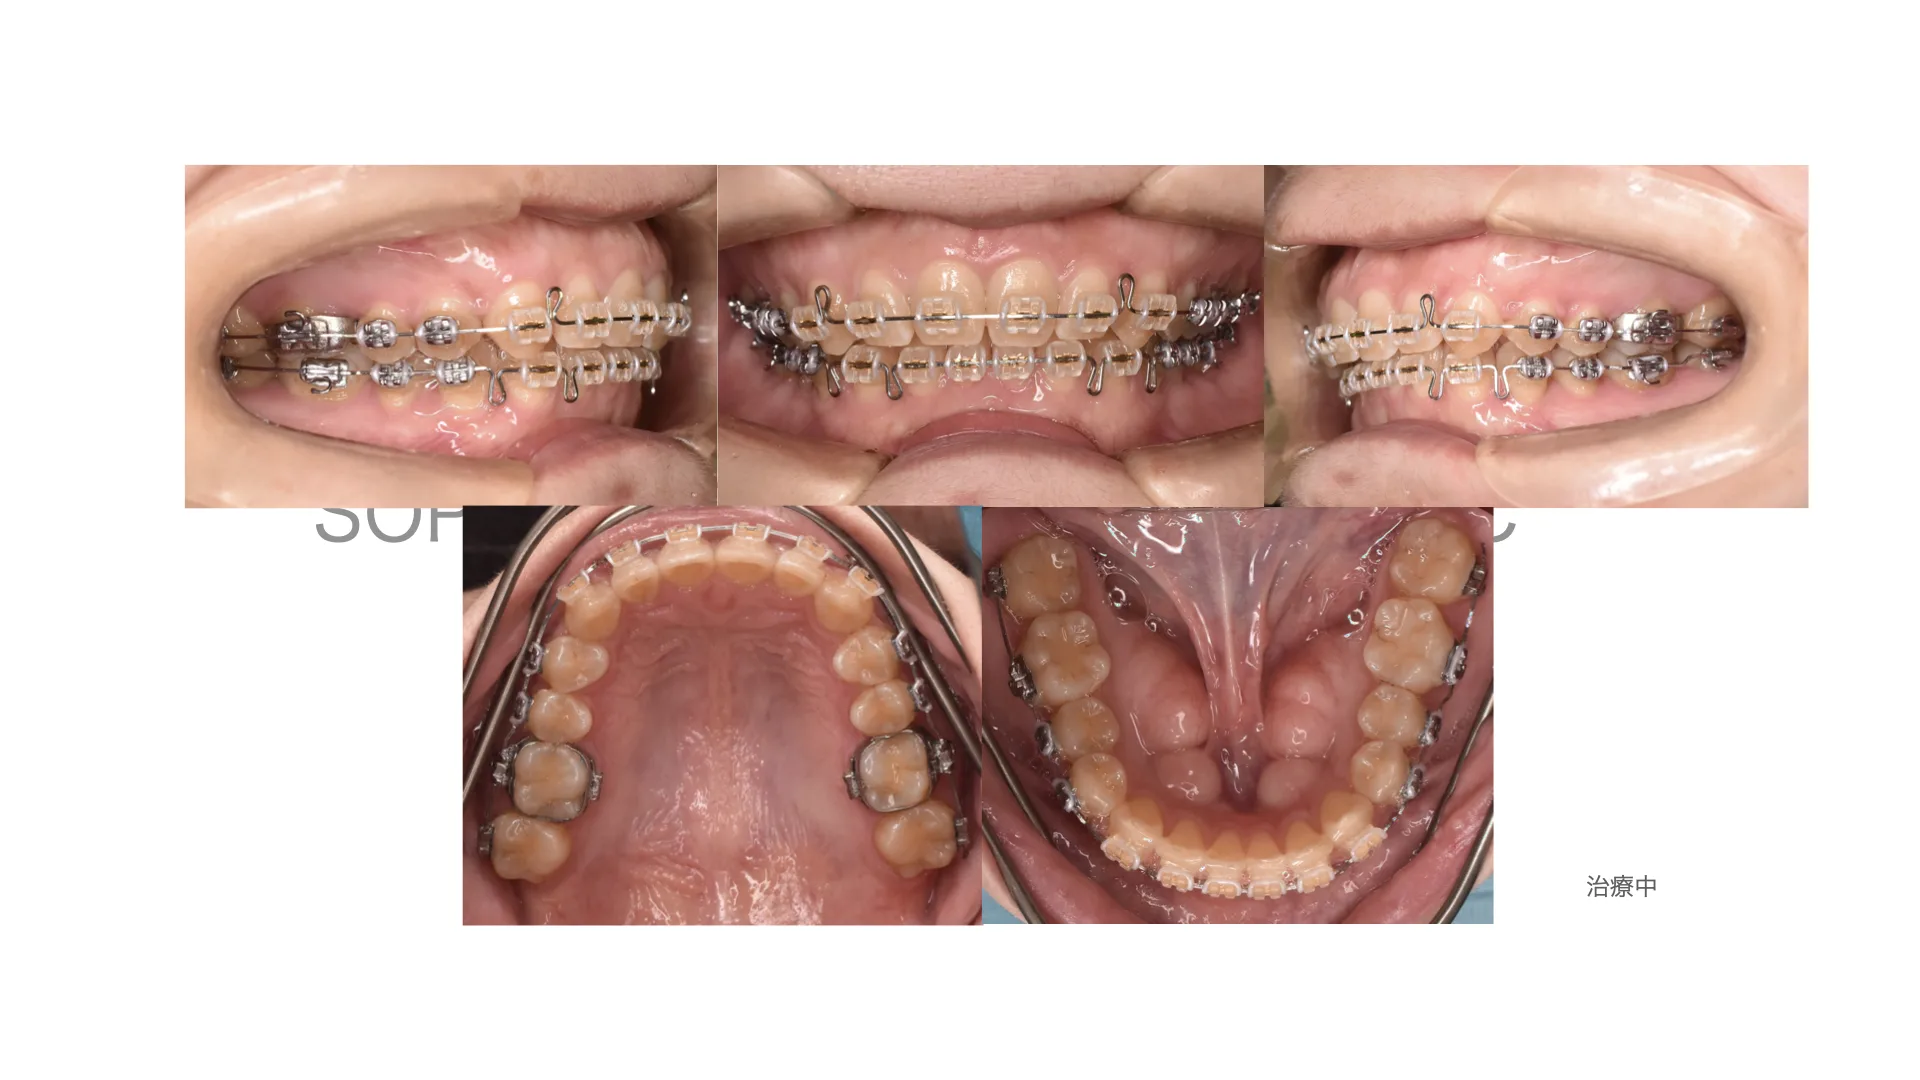

開咬症例 抜歯 唇側